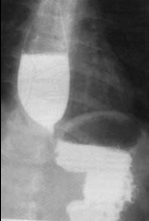

Image

radiologique de deux type de stenose oesophgienne

congenitale 1a, 2 et 1b en fusiforme , en flammeche

et abrupte |

|

Stenose

congenitale oesophagienne avec oesophagite

peptique(RGO). Oesophage en achalasia . |